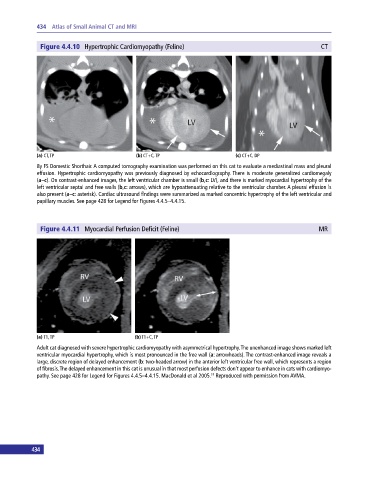

Figure 4.4.10 Hypertrophic Cardiomyopathy (Feline) CT

(a) CT, TP (b) CT+C, TP (c) CT+C, DP

8y FS Domestic Shorthair. A computed tomography examination was performed on this cat to evaluate a mediastinal mass and pleural

effusion. Hypertrophic cardiomyopathy was previously diagnosed by echocardiography. There is moderate generalized cardiomegaly

(a–c). On contrast‐enhanced images, the left ventricular chamber is small (b,c: LV), and there is marked myocardial hypertrophy of the

left ventricular septal and free walls (b,c: arrows), which are hypoattenuating relative to the ventricular chamber. A pleural effusion is

also present (a–c: asterisk). Cardiac ultrasound findings were summarized as marked concentric hypertrophy of the left ventricular and

papillary muscles. See page 428 for Legend for Figures 4.4.5–4.4.15.

Figure 4.4.11 Myocardial Perfusion Deficit (Feline) MR

(a) T1, TP (b) T1+C, TP

Adult cat diagnosed with severe hypertrophic cardiomyopathy with asymmetrical hypertrophy. The unenhanced image shows marked left

ventricular myocardial hypertrophy, which is most pronounced in the free wall (a: arrowheads). The contrast‐enhanced image reveals a

large, discrete region of delayed enhancement (b: two‐headed arrow) in the anterior left ventricular free wall, which represents a region

of fibrosis. The delayed enhancement in this cat is unusual in that most perfusion defects don’t appear to enhance in cats with cardiomyo-

pathy. See page 428 for Legend for Figures 4.4.5–4.4.15. MacDonald et al 2005. Reproduced with permission from AVMA.